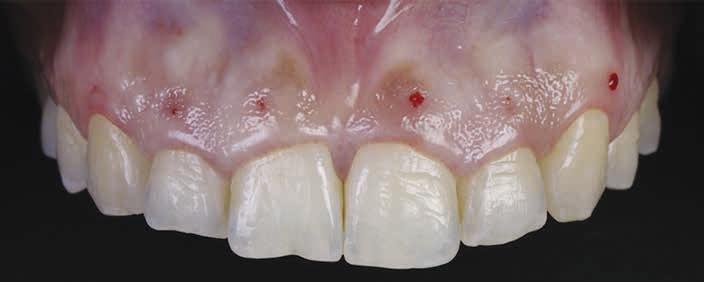

Bleeding Points (bone sounding)

The esthetic crown lengthening procedure has traditionally been guided on the basis of clinical evaluation of parameters using direct visual assessment and bone sounding.28 The clinician pierces through the gingival tissues with a periodontal probe, thereby creating bleeding points (Figure 2). These points are then connected in a scalloped fashion to represent the future gingival outline.28,29 Soft tissue can

Figure 2. Bleeding points as a guide.

be removed with either a surgical blade or using laser technology, which might be advantageous in achieving better hemostasis, especially in cases of external bevel gingivectomies. A flap is then elevated to preform resective osseous recontouring, rendering the bone crest 2 through 3 mm from the newly outlined gingival margins and thereby limiting the amount of gingival rebound.28 The amount of bone resection should be gradually reduced toward the line angles to avoid loss of interdental attachment and resulting in black triangles.